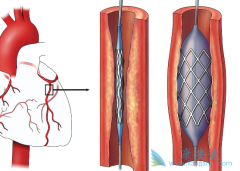

什么是 心脏支架手术 ?可以把心脏支架想象成是个细长的金属笼子,放在血管里就可以把即将堵死的血管撑开,心脏支架非常的细小,直径大约在2~4毫米,长几厘米,有空心、圆柱、网状金属管,一般都是用钛合金制成,是世界上最昂贵的一种金属。 心脏支 ...

不少人都听过心脏支架手术,这种手术堪称是当代心脏病学最伟大的一项发明。你知道这个小小的支架是怎么放到心脏里去的吗? 心脏支架 是通过介入手术的方式植入到人体的,我们可以从心脏介入手术可是说起,这样更好理解。心脏介入原理其实并不复杂。 ...

为了改善冠心病介入治疗短期和长期的疗效与安全性,所以研发了支架。第一代支架是金属裸支架,使冠心病介入治疗前进了一大步,使介入治疗变得非常安全,当血管发生严重狭窄时单纯球囊扩张预处理后,再用支架把血管完全撑开,就能解除心肌缺血危险,而且 ...

心脏支架 选哪种?放最好的支架?还是放最贵的支架?今天就给大家答疑解惑!心脏支架由具有强支撑力的合金制成,不同厂家支架的金属结构略有差别。心脏支架没有植入体内之前,包裹在球囊外面。植入时给球囊加压,支架打开至预定直径,使支架与血管壁完 ...